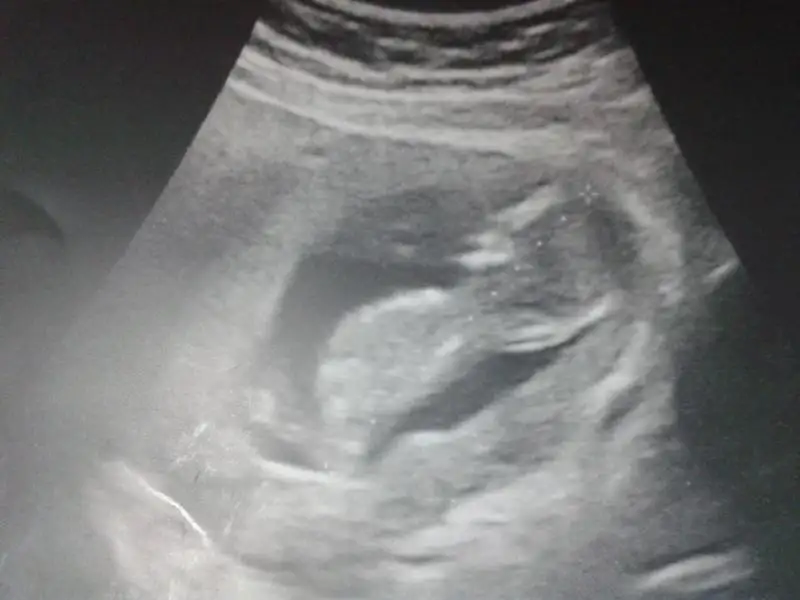

dr soylemeden siz gorun genital nub teorisi ( bebegin cinsiyeti)

maral dün doktordaydım erkeğe benziyor dedi 2 hafta sonra netleşecek ...Rabbim dileyen herkese yaşatsın bu duyguyu ihtimali bile çok güzelmiş....